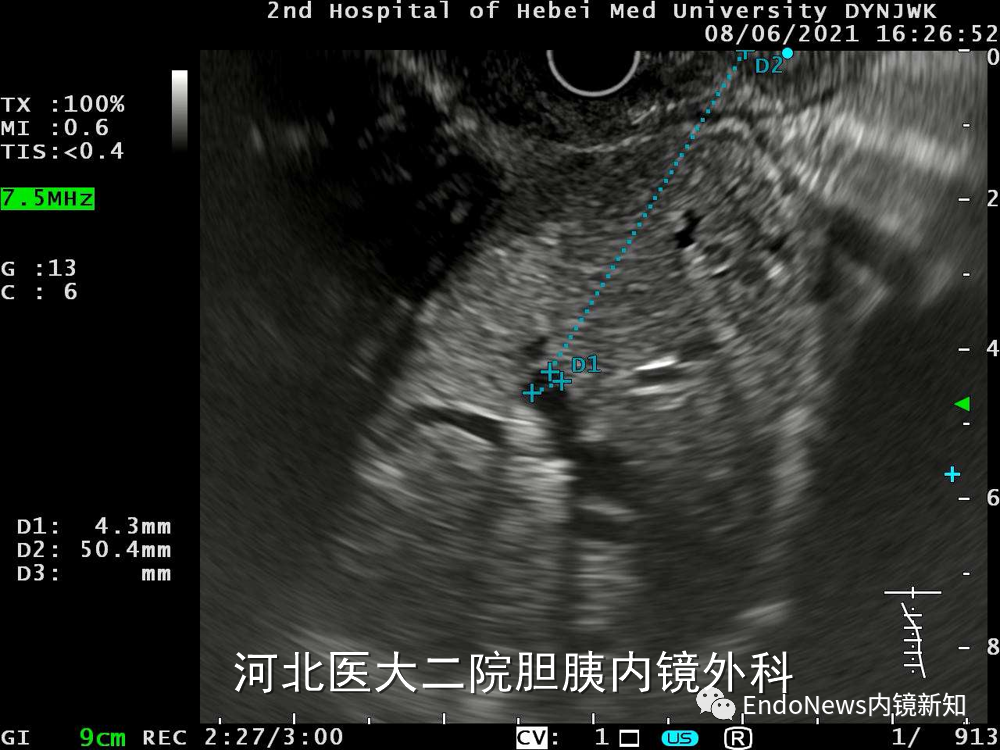

病例1患者的肝内胆管均比较细,操作难度比较高。对于这个病例,我们起初的方案是从S2段穿刺,这个位置距离比较近,但后来发现此位置的胆管才1.8mm,无法成功穿刺。

随后我们调整方法,试图从S3段穿刺,此位置胆管有2.7mm,但整个胆管扩张不是特别明显,并不是适合的位置,因此也放弃了S3段。

病例1:导丝从上游→胆管下游

最后,我们寻找到一个更适合的胆管,扩张情况较好(有可能是S4段胆管),大概在3.5mm至4.3mm之间,但这个位置也有其缺点,其距离超过5cm,因为这时候其实穿刺针的方向比较难把握的,由于肝内距离较长,进肝后很难再次调整穿刺针方向。

幸运的是,此患者第一针穿刺即成功,随后注射造影剂(EACP),显影后可观察到如图1(a)中所示,这个患者肝内胆管分支很多,但是由于每支均比较细,不容易找到理想的目标穿刺胆管。